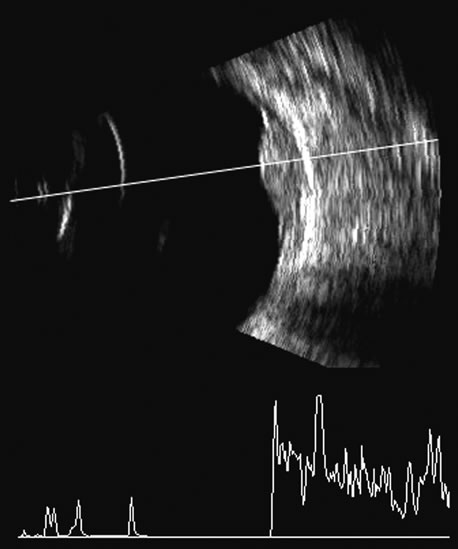

Hemorrhage shows good echogenic properties and presents a typical highly reflective vitreous body (Figs. 9 and 10). Asteroid hyalosis may resemble a vitreous hemorrhage except that the individual calcium deposits are even more reflective than hemorrhage and usually there is a clear anechoic zone between the retina and the retracted primary vitreous (Fig. 11). Synchysis scintillans is another condition with highly reflective regions in the vitreous due to cholesterol crystals. It is identifiable by the kinetic scan pattern of floating “snowflakes” that settle when the eye stops moving, just like the snowflakes in a child's snow globe. Since the “normal” vitreous is usually dissolved in this condition, the echoes come to rest on the retinal surface when the eye stops moving.

Fig. 9. B-scan ultrasonogram at 10 MHz demonstrating vitreous hemorrhage with blood accentuating the separation of the posterior hyaloid from the retina. Blood echoes vary with the length of time since the bleeding episode. Fresh blood may be relatively anechoic. Blood can produce relatively solid echoic debris or, with time, areas of fluid loculation. Blood is not easily differentiated from other debris as in uveitis.